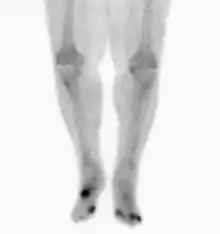

Nuclear medicine scans can be a helpful adjunct to MRI in patients who have metallic hardware that limits or prevents effective magnetic resonance. Generally a triple phase technetium 99 based scan will show increased uptake on all three phases. Gallium scans are 100% sensitive for osteomyelitis but not specific, and may be helpful in patients with metallic prostheses. Combined WBC imaging with marrow studies has 90% accuracy in diagnosing osteomyelitis.[26]